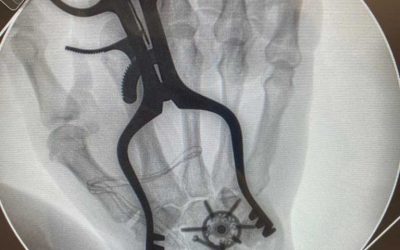

Caso de artrodesis de tobillo aplicado con innovación para artrosis avanzada

Feb 17, 2024

¿Qué es la artrodesis de tobillo para la artritis avanzada? La artritis es una inflamación de las articulaciones que...